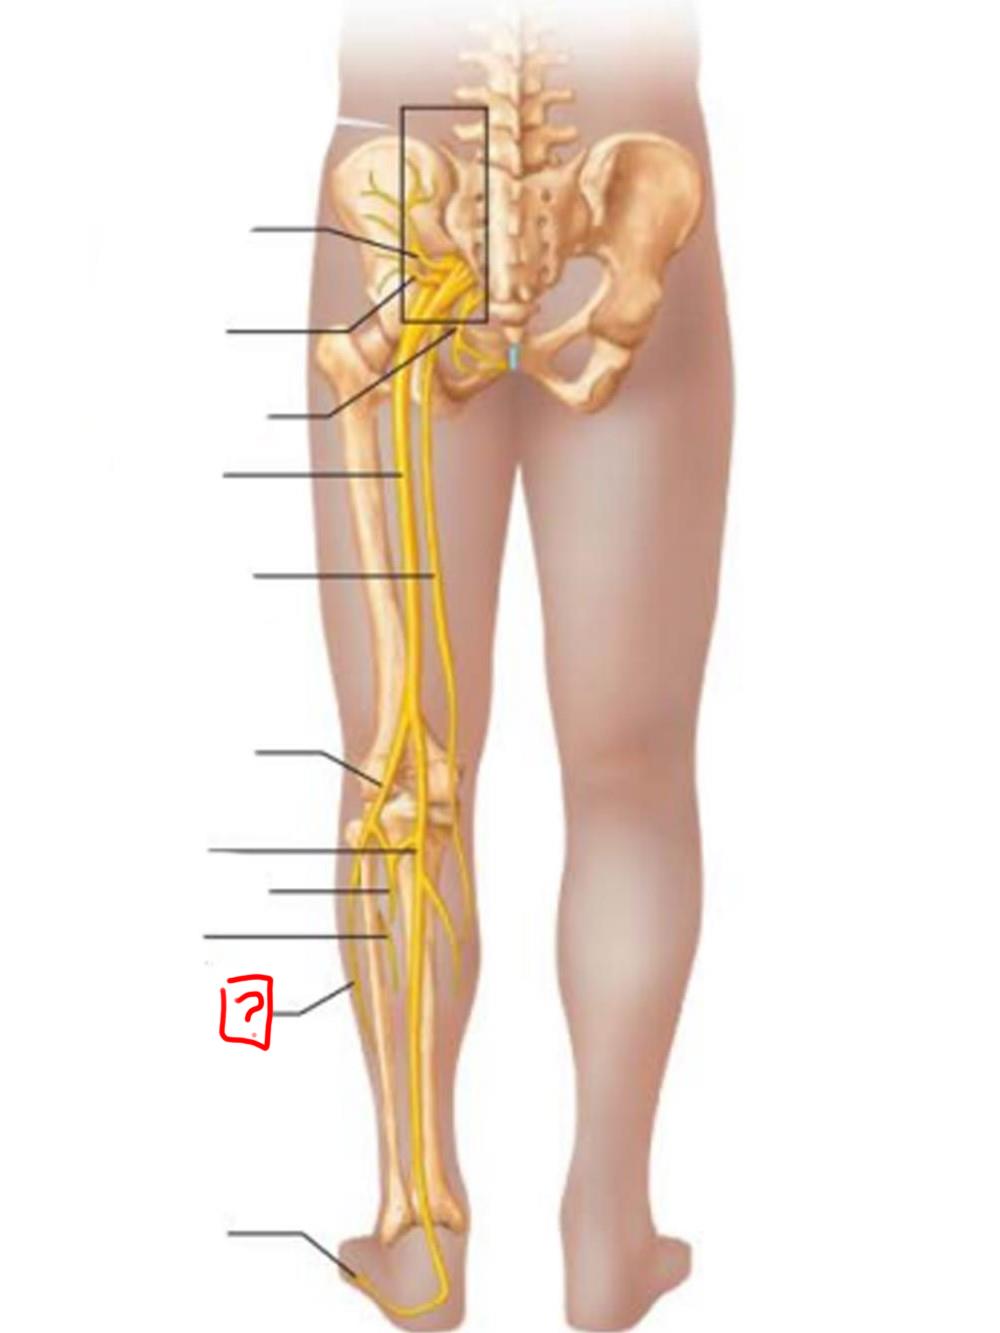

lumbosacral trunk

superior gluteal

inferior gluteal

pudendal

sciatic

posterior femoral cutaneous

common fibular

tibial nerve

sural (cut)

deep fibular

superficial fibular

plantar branches